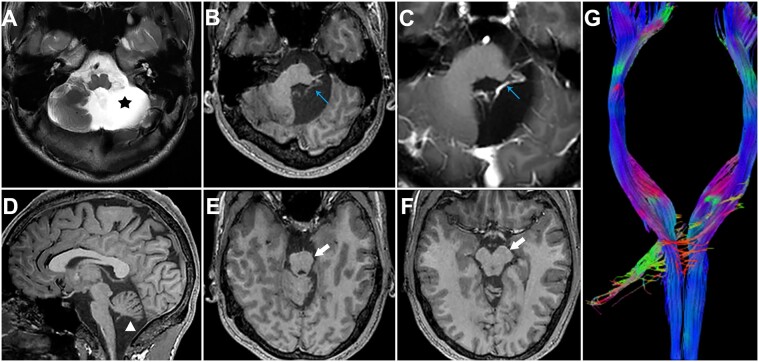

成人获得性小脑疾病的临床表现往往超过先天性小脑疾病,这表明小脑在大脑发育过程中发挥着重要作用。此外,结构和功能磁共振成像的新证据表明,小脑不仅与运动功能有关,还与认知、情感和语言等非运动领域有关。然而,要确定防止运动或非运动功能障碍所需的小脑发育的具体程度仍具有挑战性。在这项研究中,我们发现了两例新的单侧小脑发育不全病例。其中一人的生活几乎正常,而另一人则表现出轻度认知障碍、轻度抑郁和严重的自闭症,但仍保持正常的运动功能。Van der Heijden 等人(2023 年)发现,大脑可以补偿发育中的小脑所受到的一些干扰,包括运动障碍和社交行为障碍。因此,我们假设,对比我们患者的结构图像并回顾相关文献,可能会阐明小脑发育不全患者出现不同临床表现的原因。

The clinical manifestations of adult-acquired cerebellar diseases often surpass those of congenital cerebellar diseases, suggesting the significant role of the cerebellum in the developing brain. Moreover, emerging evidence from structural and functional magnetic resonance imaging indicates that the cerebellum is implicated not only in motor functions but also in non-motor domains such as cognition, emotion, and language. However, delineating the specific extent of cerebellar development required to prevent deficits in either motor or non-motor functions remains challenging. In this study, we present two new cases of unilateral cerebellar agenesis. One individual leads a nearly normal life, while the other exhibits mild cognitive impairment, mild depression, and severe autism, but maintains normal motor function. Van der Heijden et al. (2023) revealed that the brain can compensate for some, but not all, perturbations to the developing cerebellum, including motor deficits and impairments in social behaviors. Therefore, we hypothesize that comparing structural images from our patients and reviewing pertinent literature may elucidate the reasons for the varied clinical manifestations observed in patients with cerebellar agenesis.